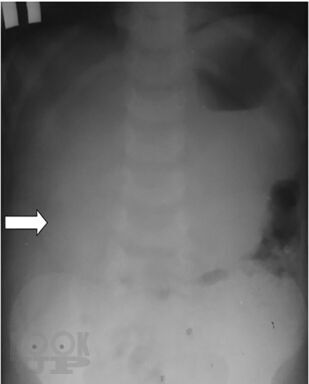

В монографии изложены наиболее актуальные вопросы диагностики и лечения кишечной инвагинации у детей. Представлены данные по истории вопроса, классификация заболевания, диагностический алгоритм. Рассмотрены наиболее частые ошибки в диагностике этого заболевания у детей, подробно обоснован выбор лечебной тактики на основании экспериментального;исследования безопасности консервативного лечения инвагинации кишечника в педиатрической практике. Описаны методики консервативного лечения этого состояния у детей, представлен анализ собственных практических результатов их применения. Отдельно рассмотрены вопросы оперативного лечения инвагинации кишечника у детей, приведено экономическое сопоставление методов лечения этого состояния.